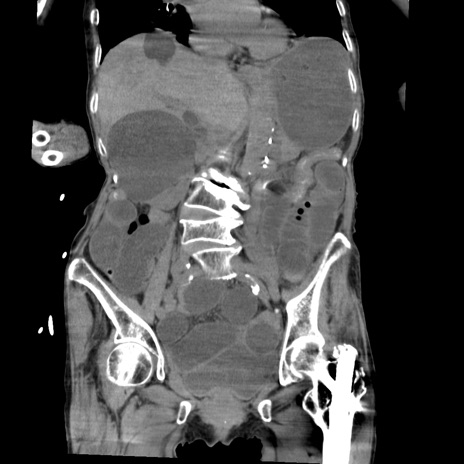

症例27(冠状断像)

【症例】80歳代女性

【主訴】嘔吐、腹痛

【現病歴】数時間前より嘔吐あり。心窩部痛出現し、徐々に右下腹痛あり。その後も数回嘔吐あり救急搬送となる。

【既往歴】左大腿骨頚部骨折手術

【身体所見】腹部は膨隆しているが軟らかく圧痛なし。腸雑音はやや亢進。

【データ】WBC 12000、CRP 19.05